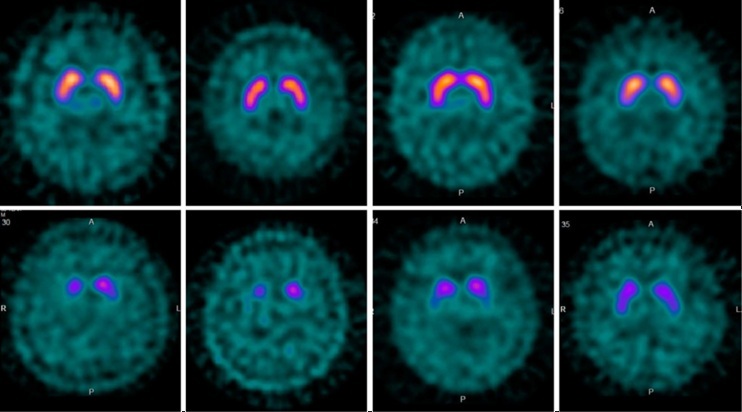

パーキンソン症候群の頭部MRI

上段:本態性振戦,薬剤性パーキンソニズム,SWEDDs,AD,

下段:PD,MSA,PSP,DLB

SWEDDs= scan without evidence of dopaminergic deficits